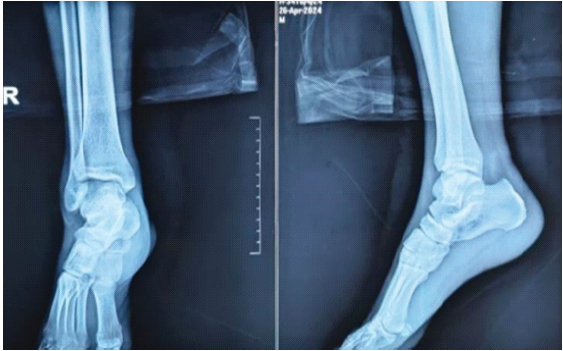

After taking due informed consent, the patient was taken to the operation theatre after 3 h of his arrival. He was placed in a supine position on the operating table. General anesthesia was administered and airway secured. A tourniquet was used at an appropriate pressure to aid in the procedure. The vascular surgery team was informed to be in standby mode. Removal of blade from the ankle was attempted first. Incisions were given at the entry and exit wounds, and a thorough wash was given. The metallic blade was removed with a single pull. Twists and turns were avoided to prevent any iatrogenic damage to the surrounding structures [4]. The area was thoroughly washed once more with normal saline and diluted betadine. Incisions were then carefully made without deep dissection at the entry and exit wounds in the knee. A light mallet was used to gently strike at the anterior aspect of the metallic blade in a controlled manner. The rod was then removed with a single pull. Along with the blade, the entire portion of the torn clothing was removed. Careful debridement was then done at both sites (knee and ankle) along with copious irrigation. Complete removal of the objects was confirmed clinically and through fluoroscopy. Gentle examination under anesthesia (Joint stability tests) was then performed, which suggested ligament injuries in both sites. The tourniquet was then deflated to check for any inadvertent arterial injury. SpO2 of the limb was >94%. Once the absence of arterial injury was confirmed, the wound was closed in layers. An above-knee anterior slab was put for adding stability of the joints and injured soft tissues. The post-operative radiograph documented the absence of any foreign bodies. Post-operatively an magnetic resonance imaging (MRI) was also done, which confirmed lateral meniscus and lateral collateral ligament injuries, anterior talofibular, calcaneofibular and tibiotalar ligaments in both the knee and the ankle, respectively. Absence of any retained clothing was also confirmed in the MRI. His post-operative hospital stay was mostly uneventful except for a superficial wound infection at the popliteal entry wound that eventually healed with IV antibiotics, single debridement, and regular dressings. The sutures were removed at the end of the 2nd week. The patient was then discharged in satisfactory clinical condition with the explanation that he may eventually require knee and ankle arthroscopy and reconstruction of some of the critically torn ligaments of the knee and ankle joint if these fail to heal satisfactorily (Fig. 6, 7, 8, 9, 10).

Figure 10: Post-operative (Anteroposterior and Lateral) radiograph of the right ankle.